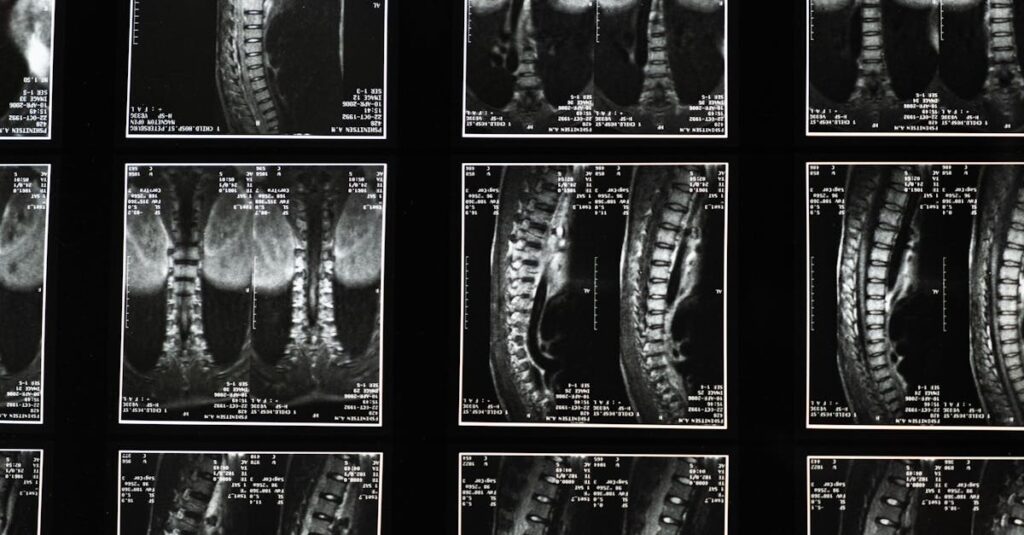

Technologie Modernes

Imagerie médicale, applications de suivi de santé.